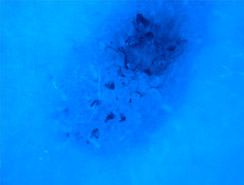

Lo studio e la diagnosi delle neoformazioni cutanee attraverso strumenti specifici indicati per un'analisi delle caratteristiche strutturali superficiali e profonde delle varie neoformazioni cutanee: dermatoscopia, dermalite a luci fotocromatiche, mappatura nevica con videodermatoscopia digitale.